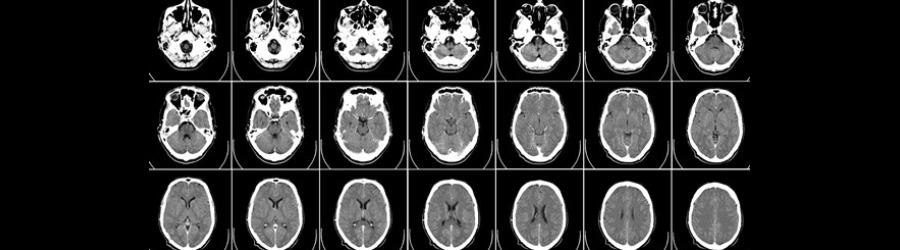

Find out what happens in the brain when we learn and create memories, and why we shouldn’t always trust everything we remember. By understanding our brains better, we can find ways to help improve these processes, at any stage of our lives. During the course, you will find out how memories are stored in the brain, how this process can go wrong, and what changes in the brain as you age. Using research from psychology and neuroscience, we will also cover tips and tricks to help you make the most of your memory.